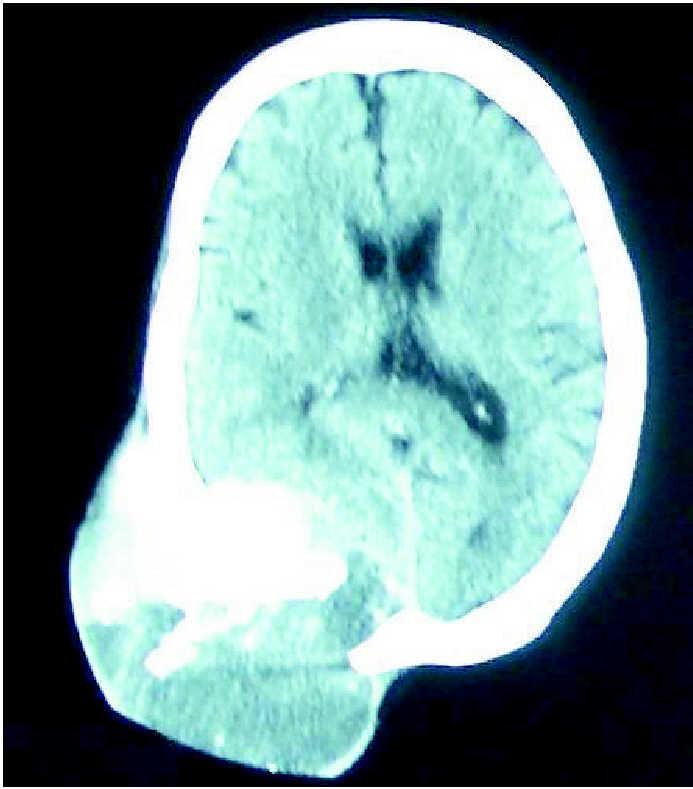

Ante la progresión del tamaño de la lesión occipital, pese a la radioterapia recibida, se plantea la posibilidad de extirpar dicha lesión. Se repite la TC craneal, en la que se visualiza una extensa imagen lítica que afecta al occipital derecho, y se acompaña de gran masa de partes blandas de 12 × 10 × 9 cm, que invade los espacios cutáneos y epidural (fig. 4).

Figura 4.Imagen lítica que afecta al occipital derecho y se acompaña de gran masa de partes blandas, redondeada, que invade los espacios cutáneos, así como el área epidural.